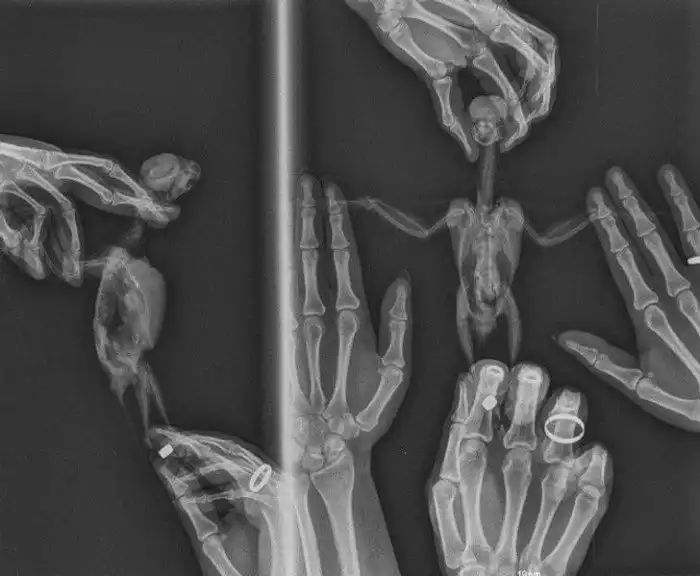

2. "Так попугаю делают рентген. Птица живая и с ней все хорошо. Процедуру проводил ветеринар, и мы были там, чтобы помочь удержать нашего питомца"